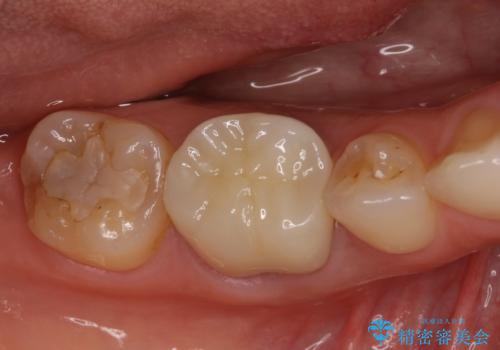

部分矯正を併用した奥歯のインプラント治療